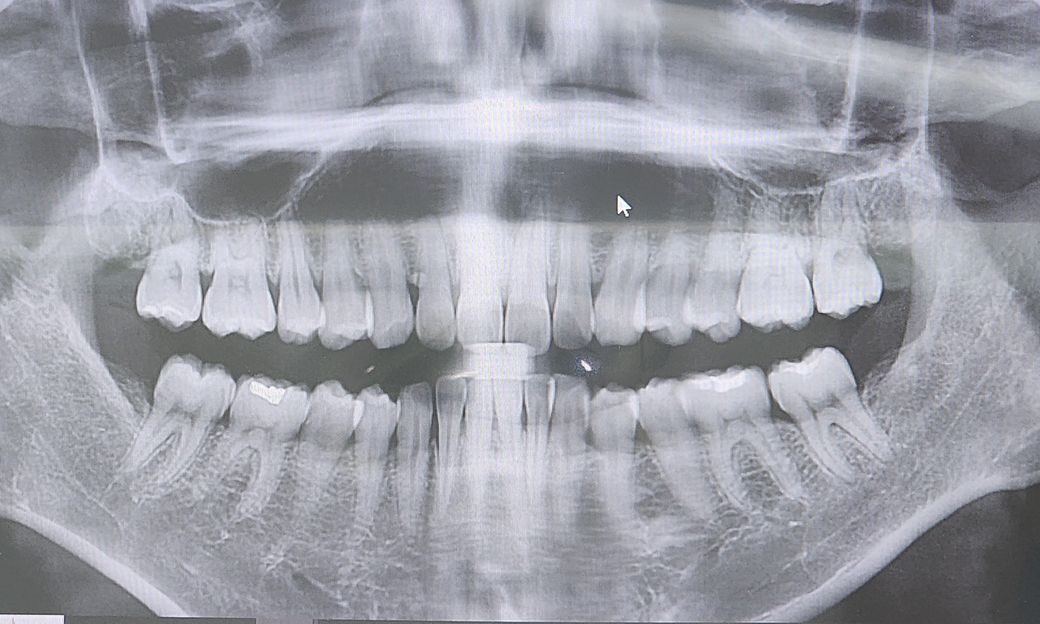

30대입니다 혹시 잇몸퇴축이 심한가요??ㅠㅠ 잇몸퇴축이 심하면 치과에서 치료받으면 다시 차오르나요?? 잇몸영양제도 추천부탁드려요 ㅠㅠ 송곳니쪽이랑 아래 어금니쪽이 뭔가 많이 내려간것처럼보이는데 ㅜㅜ 괜찮은건가요

나이에 비해 잇몸퇴축이 심한편은 아닙니다

사진으로 봤을 경우에는 잇몸 퇴축이 심한 것으로 보이지는 않습니다. 너무 걱정하지 않으셔도 될 것으로 생각됩니다.

이정도면 정상적인 잇몸입니다. 한번 내려간 잇몸은 도로 회복안됩니다. 잇몸 내려가지 않게 평소 꼼꼼한 치솔질과 정기적인 스켈링 필요합니다. 아직까지 잇몸에 좋은 그런 영양제는 없습니다. 평소에 채소나 과일 자주 드시면 잇몸건강에 도움이 됩니다.